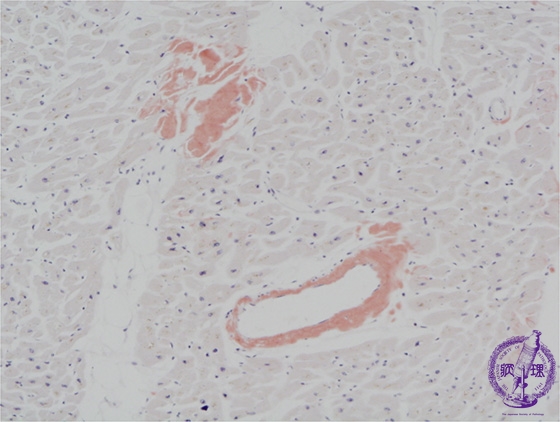

Microscopic image (Congo-red stain, low power view): There are small deposits of amorphous substance on HE staining composed of amyloid as demonstrated by Congo red stain (arrow). Amyloid deposition is confirmed by polarized light microscopy, which shows focal apple green birefringence.